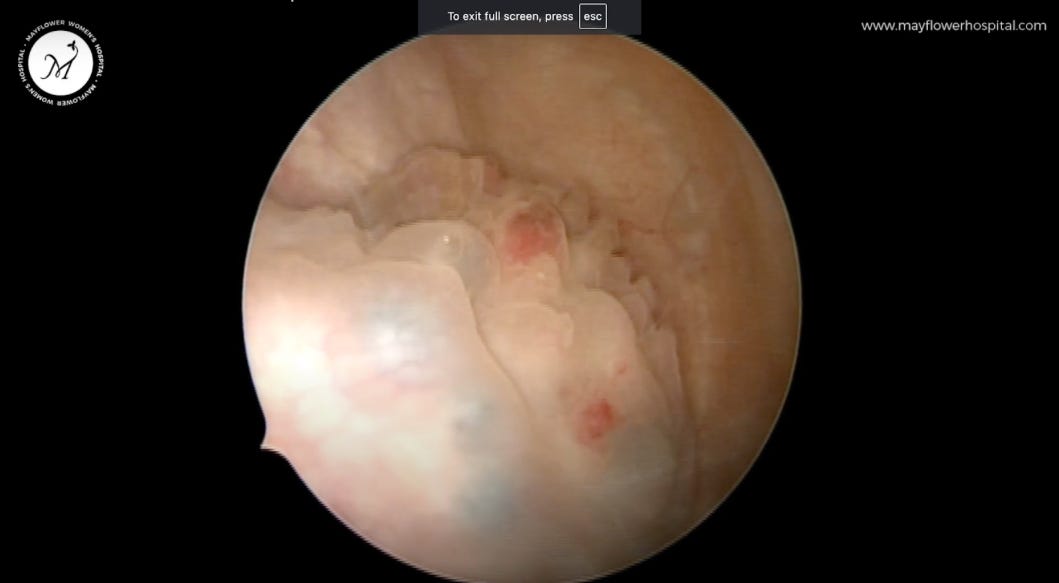

Alright, let’s jump in now. Once we’ve mapped the disease, we must confirm it. Surgery begins with a cystoscopic view from inside the bladder where we mark the disease.

The ureteric orifice and trigone area appear normal but we can see some endometriosis plaque buildup involving the mucosa on the dome of the bladder.